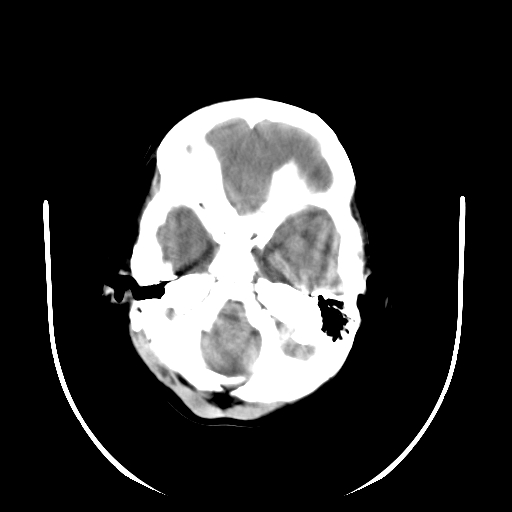

以下是引用深泽交通医院在2009-10-16 8:25:00的发言:[br]右眼环出血伴异物

以下是引用卜一在2009-10-16 15:01:00的发言:[br]右眼球挫裂伤伴异物!

以下是引用拾荒者在2009-10-17 18:38:00的发言:[br]鼻面部皮下积气,右侧睑缘及眼球壁高密度异物影,左侧眼球壁晶状体内侧缘处是圆形低密度影。低密度异物?应提请眼科医生注意。